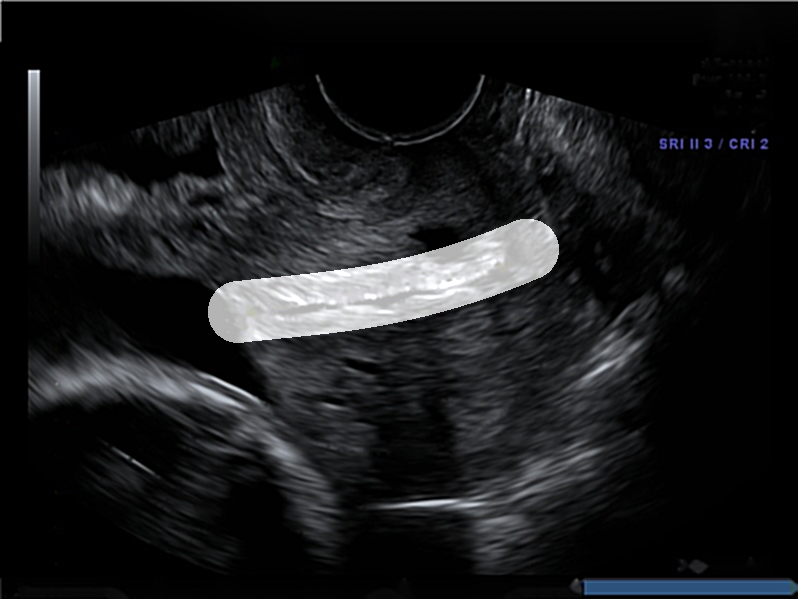

Dataset: The original dataset consists of 354 two-dimensional transvaginal cervical ultrasound images. Data were collected from female volunteers during check-ups conducted in the first and second trimesters of pregnancy. Data includes 319 images of the pregnancy control group and 35 images of premature deliveries which reflects the statistical occurrence of this phenomenon in reality. Note that to get information about image labels, we waited for the pregnancy result of each patient. The data was provided by two different clinics: King’s College London and Medical University of Warsaw. All images have been annotated by several independent gynecologist experts via our own annotation tool. Sample images from the data set are depicted in Fig. 1.

The annotations received contained the study identifier and four control points which allowed for the drawing of cubic Bézier curves that outlined the shape and position of the cervix in the image. Bézier curves were used to create masks for cervical segmentation.